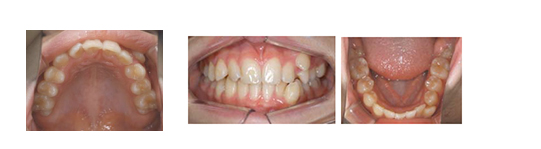

上の親知らずが萌出して噛み合わせに参加しています

矢印の歯を抜歯しましたが、

親知らずが萌出しています